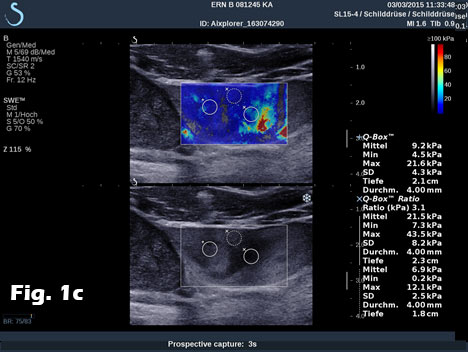

We report on the incidental finding of a 70 y/o patient presenting with an indolent cervical swelling and mass. Clinical examination and laboratory data were not conclusive. In the figure sequence B mode ultrasound and shear wave elastography revealed a 43 mm mass lesion with peripherally stiffer tissue (a) with thrombosis in statu nascendi of jugular vein shown by B mode (b) and also by contrast enhanced ultrasound (c) and shear wave elastography (d). 3D shear wave elastography confirmed the circumscript peripherally stiffer cervical mass (e). 3D SWE added complementary information for a better delineation of the distribution of increased stiffness, following the fibrous capsule around the nerve. SWE also showed feasibility to demonstrate stiffer tissue within jugular vein. 3D techniques allowed improved documentation of the anatomical volume including the tumour and surrounding vessels [(1-3)]. Histologically the nerve tumour schwannoma was proven.

Figure 1:B mode ultrasound and shear wave elastography revealed a 43 mm mass lesion with peripherally stiffer tissue (a) with thrombosis in statu nascendi of jugular vein (b), also shown by contrast enhanced ultrasound (c) and shear wave elastography (d). 3D shear wave elastography confirmed the circumscript peripherally stiffer cervical mass (e).